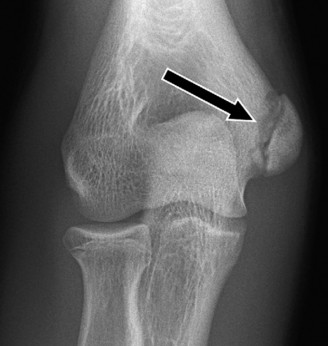

Treat a patient with infected total shoulder arthroplasty? CASE 21 A 70-year-old, right-hand-dominant female presents to clinic complaining of 4 years of gradually worsening chronic right shoulder pain and stiffness. She says the pain is worse at night and with any range of motion, denies a history of trauma, pain in other extremities, or numbness or tingling of the right upper extremity. She notes that her mother suffered from rheumatoid arthritis that affected her shoulder. Physical examination reveals decreased muscle bulk over the right supra- and infraspinatus fossae compared to the contralateral side, limited active and passive ROM, marked weakness with external rotation, and 4+/5 strength with shoulder abduction. X-rays of the right shoulder are shown in Figures 2–58 and 2–59.

Figure 2–58

Figure 2–59

The correct answer is (C). Rotator cuff tear arthropathy consists of a combination of rotator cuff insufficiency, glenohumeral joint degenerative changes, and superior humeral head migration. It is more common in women and also more often found on the dominant side. The patient’s clinical examination with weakened external

rotation and muscle atrophy signaling incompetent supra- and infraspinatus muscles point to rotator cuff insufficiency, and her plain films reveal narrowed glenohumeral joint space as well as superior migration of the humeral head. Choice D is incorrect because, while radiographs would show narrowing of the glenohumeral joint space, they would also likely show numerous osteophytes and posterior wear of the glenoid. Choice B is incorrect because, while adhesive capsulitis does present as decreased active and passive range of motion, the patient’s constellation of symptoms pointing towards rotator cuff insufficiency along with the radiographs make cuff tear arthropathy the more likely choice. Finally, Choice A is incorrect because even though she has a positive family history of rheumatoid arthritis, it is less likely to present only in a single joint. Also, rheumatoid arthritis on radiography appears more as an erosive process without the characteristic superior migration of the humeral head.

The correct answer is (A). Superior migration of the humeral head would be most indicative of chronic rotator cuff insufficiency associated with cuff tear arthropathy, as it is a direct result of the inability of the rotator cuff tendons to help maintain the humerus in its normal position. Acetabularization of the undersurface of the acromion is commonly associated with superior migration of the humeral head found in rotator cuff tear arthropathy, and can be assessed using the Hamada classification, which is based on measurements of the acromiohumeral interval on radiography (Table 2–8). Choices B and C are incorrect because, while narrowed glenohumeral joint space and subchondral sclerosis are associated with rotator cuff arthropathy on radiographs, they indicate degenerative joint changes rather than chronic rotator cuff insufficiency. Choice D is incorrect because it is not a specific sign of rotator cuff arthropathy.